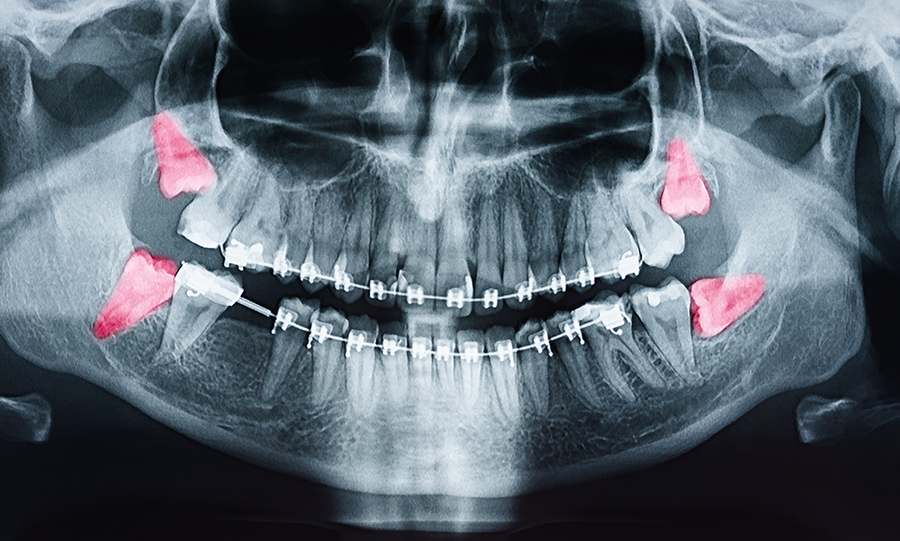

親知らずの歯は、歯の形や生えている向きが他の歯と大きく異なることが多く、様々なケースの症例があります。真横に向いている、根が極端に曲がっている、アゴの神経や血管が親知らずに接近しすぎているなどの難しい抜歯になるケースも珍しくありません。このような多くの症例に対応するためには、医科歯科の見地や、外科的知識や技術が必要とされます。当院では、大学病院での口腔外科勤務の経験から、幅広い症例に対応し、迅速かつ痛みのない親知らずの抜歯における外科治療を行っています。痛みがある、抜こうか悩んでいる、他院で断られたなど、お悩みの方はお気軽にご相談ください。

術前のカウンセリングで、抜歯の必要性を診査診断し、抜歯の必要がある場合、顎の神経に歯の根元が近くないかを確認し、安全に処置を進めていきます。歯の角度や根っこの形状をあらかじめ調べ、迅速かつ安全に抜歯します。当院では手術室をはじめ大学病院並みの設備を完備しており、抜歯における生体モニターやCT設備、検査機器を揃えています。滅菌された器具で清潔な環境を徹底しているので、安心して外科手術に臨んでいただくことができます。

埋もれている親知らずの歯の抜歯、口腔内の手術などを行う場合には、まずコンピューターでシミュレーションを行います。さらにCT画像︎を処理することで様々な角度から画像を分析し、より安全に治療を行うことが可能です。